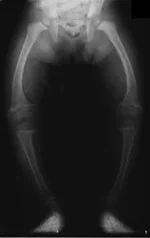

Все обсуждают ноги - рахит это называется. Х-образные или О-образные ноги. Учебник биологии за 9-й класс https://ru.wikipedia.org/wiki/Рахит

• 190px-XrayRicketsLegssmall[1].webp

190px-XrayRicketsLegssmall[1].webp

2.4 КБ · Перегляди: 82